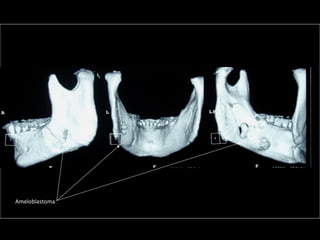

AmeloblastomaAmeloblastoma

Ameloblastoma

Trismus importante debido a queTrismus importante debido a que

El tumor ya rompió el hueso com-El tumor ya rompió el hueso com-

Pacto de la cara interna de laPacto de la cara interna de la

Mandíbula y empezó a tomar elMandíbula y empezó a tomar el

Músculo pterigoideo interno.Músculo pterigoideo interno.